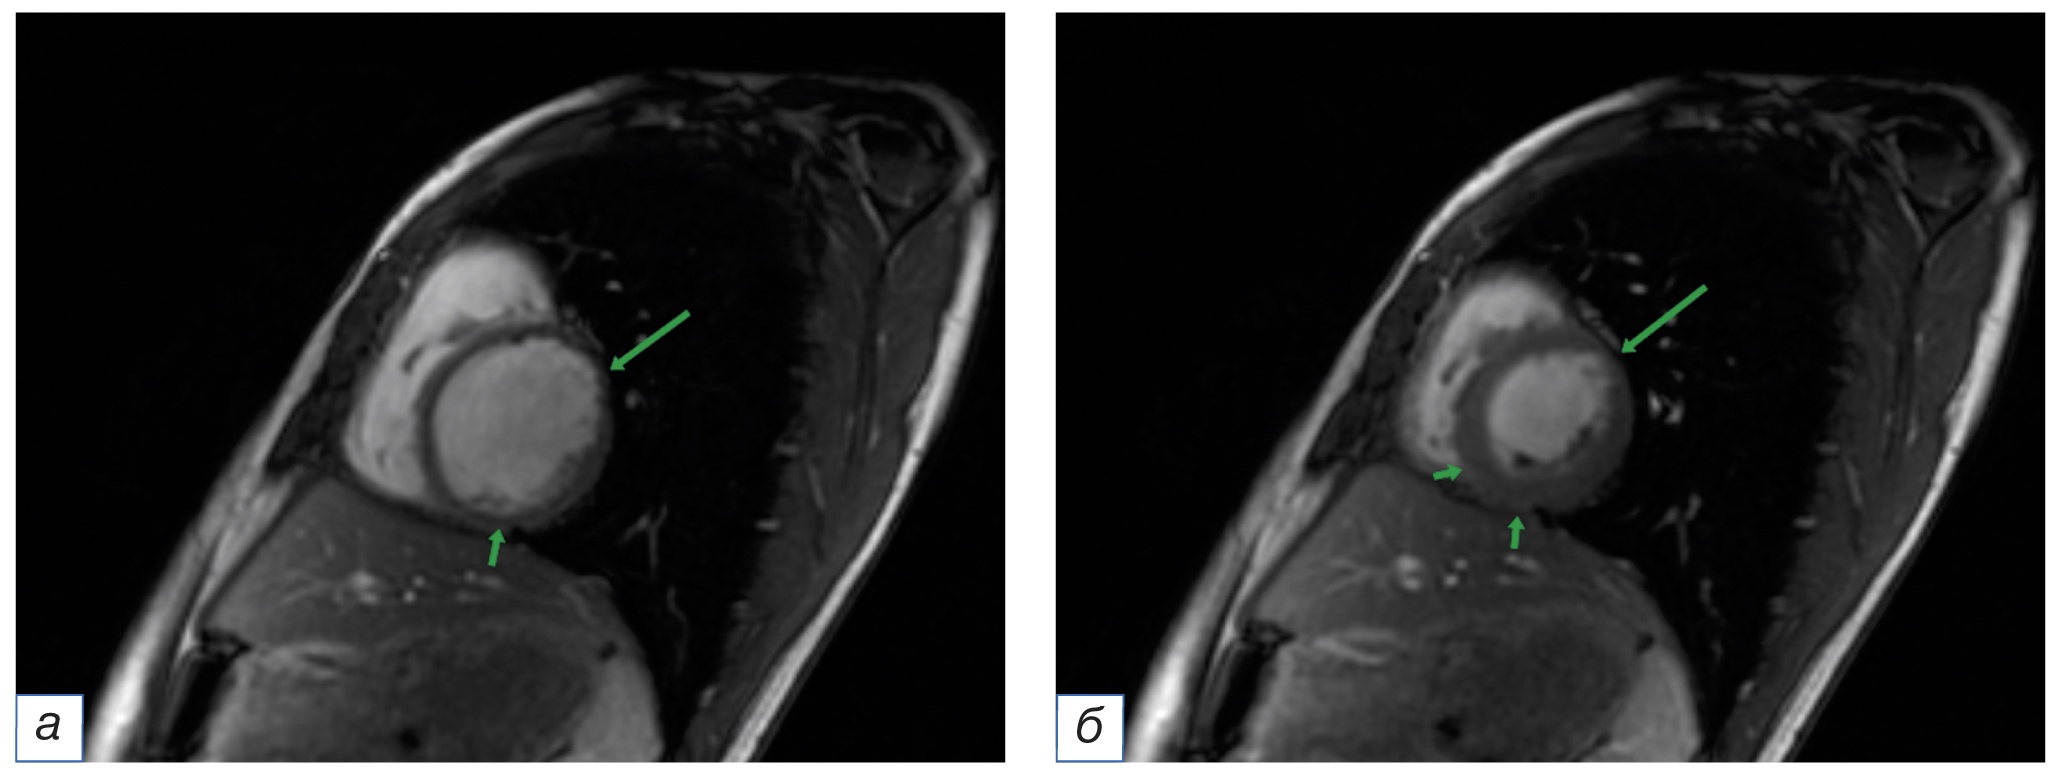

Существуют основные паттерны накопления контрастного препарата при неишемическом типе поражения сердечной мышцы, такие как субэпикардиальный и интрамуральный (рис. 4). Но нельзя исключать наличие редких случаев, в которых накопление контрастного препарата происходит субэндокардиально, как при эозинофильном эндокардите, либо по типу обширных трансмуральных участков, где выявить доминирующий паттерн затруднительно. Дифференцировать ишемическое и неишемическое повреждение миокарда можно также с помощью совпадения зон поражения сердечной мышцы с областями кровоснабжения коронарных артерий. При неишемическом типе зоны поражения не будут соответствовать бассейнам кровоснабжения коронарных артерий.

Рис. 4. Изображения по короткой оси сердца. Представлены различные паттерны накопления контрастного препарата в отсроченную фазу: а — субэпикардиальный; б — субэндокардиальный; в — интрамиокардиальный (интрамуральный); г — трансмуральный.

Fig. 4. A schematic picture along the short axis of the heart. Various patterns of delayed contrast enhancement are presented: а — subepicardial; б — subendocardial; в — intramyocardial (intramural); г — transmural.

Изменения сердечной стенки при миокардите могут сочетаться с поражением перикарда (такие варианты течения называют миоперикардитом; рис. 5) и проявляются в виде воспаления сердечной сумки или выпота. Чаще всего поражаются прилежащие к изменённому миокарду участки перикарда, но встречаются случаи диффузного воспаления. Несмотря на то, что перикардиальный выпот расценивается лишь как сопутствующий признак [34, 35], некоторые исследования демонстрируют повышение чувствительности МР-оценки миокардита при его наличии [36].

Рис. 5. Магнитно-резонансная томография сердца, отсроченная серия с контрастным усилением (MDE) по короткой оси сердца. Стрелками указаны участки накопления контрастного препарата субэпикардиальными очагами и прилежащей частью перикарда.

Fig. 5. Cardiac magnetic resonance imaging, delayed contrast enhancement series (MDE), short axis plane. The arrows indicate the areas of the contrast enhancement in the subepicardial foci of the myocardium and the adjacent part of the pericardium.